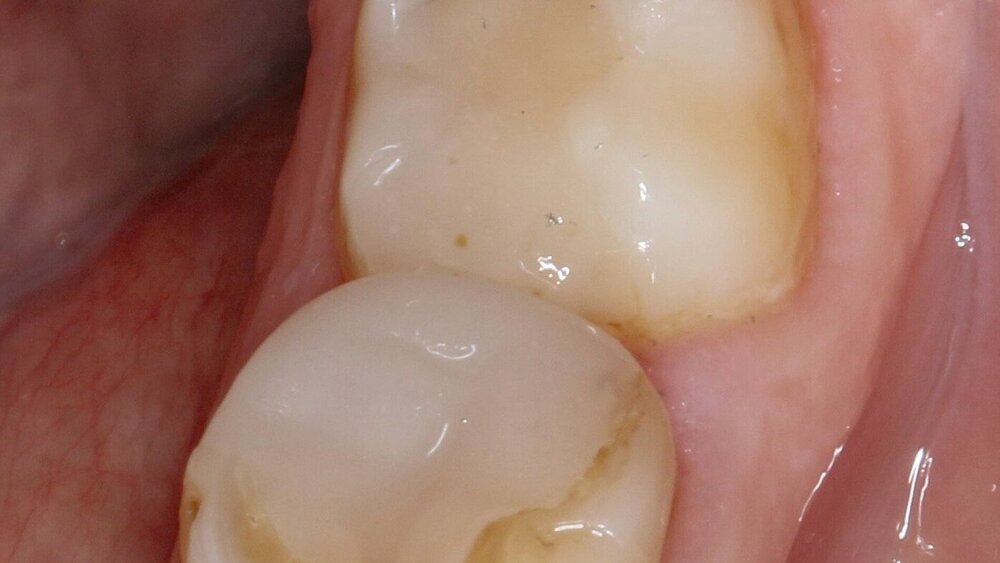

Die Arbeitsgruppe um Marco Gresnigt von der Universität Groningen, Niederlande, ermittelte nun Daten zum Langzeitüberleben von Komposit-Seitenzahnrestaurationen anhand von 88 Patienten im Alter zwischen 34 und 74 Jahren (mittleres Alter 51,3 Jahre) und 117 direkten Kompositfüllungen. Eingeschlossen wurden sowohl Prämolaren als auch Molaren, die vorher mit einer Amalgamfüllung versorgt waren. Ein weiteres, sehr wichtiges Einschlusskriterium war, dass mindestens ein Höcker bei Prämolaren und zwei Höcker bei Molaren durch die Kompositfüllung ersetzt sein mussten. Die klinische Ausführung fand in einer niedergelassenen Praxis statt. In den allermeisten Fällen wurde die relative Trockenlegung gewählt.

Da zwischen 2007 und 2013 Patienten in die Studie aufgenommen wurden, wurde ein damals etabliertes adhäsives Vorgehen gewählt: Total-Etch (37-prozentige Phosphorsäure) für 20 s, Absprühen für 5 s, relative Trockenlegung, Primerauftrag (Quadrant Unibond Primer, Cavex) für 20 s, Trocknung, Adhäsivauftrag (Quadrant Adhesive, Cavex), leichtes Verblasen, Lichthärten für 20 s, Kompositapplikation in Inkrementtechnik, jeweils 20 s Lichthärten, Okklusionskontrolle (Kontakte auf der Füllung), Ausarbeitung und Politur.